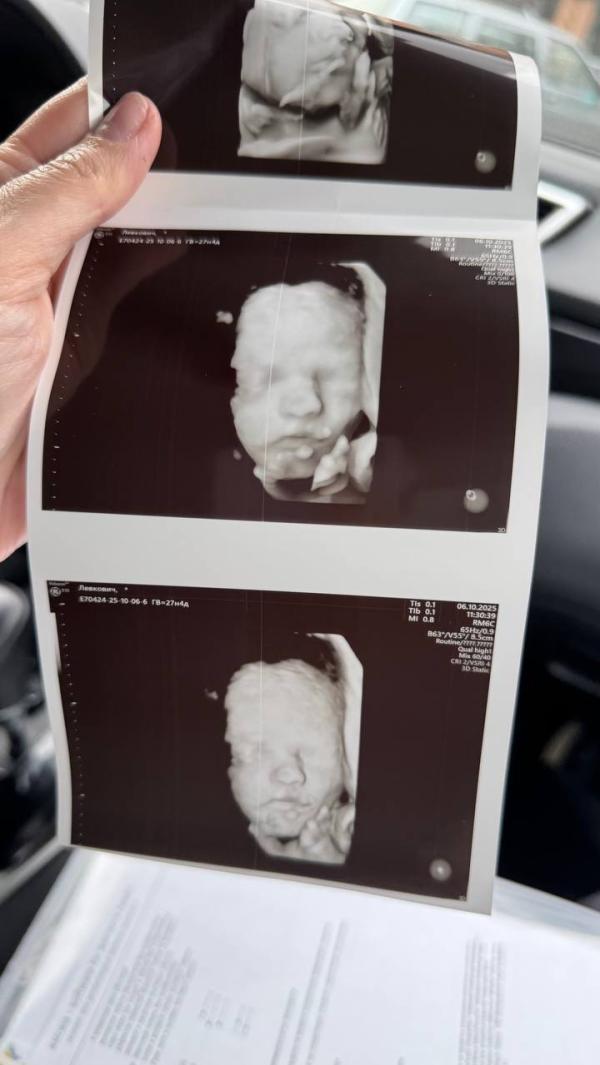

Наша дочка - ксерокопия отца: ждём встречи через месяц!

Бусинка наша получилась ксерокопия отца🥹

Остается меньше месяца и увидем её в живую